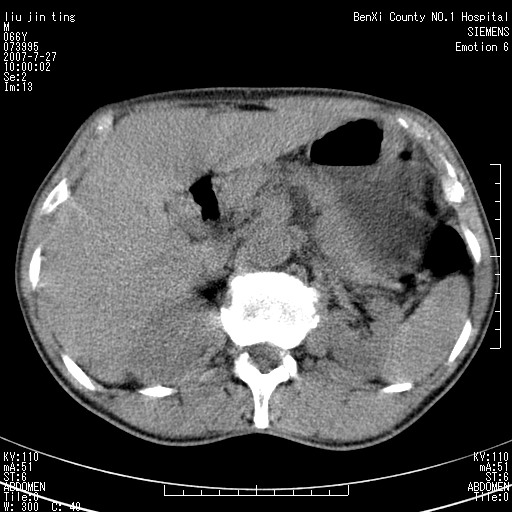

沿着肠系膜上动脉呈匍匐性生长的软组织肿块,形态不规则,包绕肠系膜上动脉,呈明显强化,考虑来源于肠系膜的恶性肿瘤

沿着肠系膜上动脉呈匍匐性生长的软组织肿块,形态不规则,包绕肠系膜上动脉,呈轻-中度强化,考虑来源于肠系膜的恶性肿瘤。

支持!恶性纤维组织细胞瘤可能,与淋巴瘤及淋巴结转移鉴别(腹主动脉周围清晰,其他部位亦未见明显肿大淋巴结)。

考虑为腹膜后恶性纤维组织细胞瘤。

后腹膜肿块,包围血管,考虑淋巴恶性病变,淋巴瘤或转移。